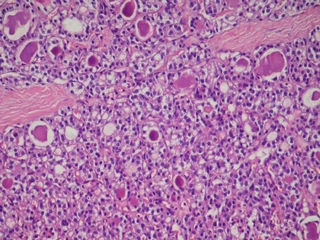

Hipertiroidizm Nedir?Hipertiroidizm, tiroid bezinin aşırı hormon üretmesi durumudur. Bu durum, gebelikte çeşitli komplikasyonlara yol açabilir. Hipertiroidizm, genellikle Graves hastalığı gibi otoimmün hastalıklardan kaynaklanır, ancak tiroidit veya tiroid nodülleri gibi diğer nedenler de olabilir. Gebelikte Hipertiroidizmin EtkileriGebelikte hipertiroidizm, hem anne hem de fetüs üzerinde olumsuz etkilere yol açabilir. Bunlar arasında: